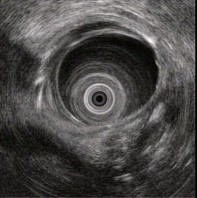

(单选题)胰腺超声内镜如图,最可能的诊断是()。

A:胆管结石

B:急性胰腺炎

C:胰腺癌

D:慢性胰腺炎

E:胰腺囊腺癌